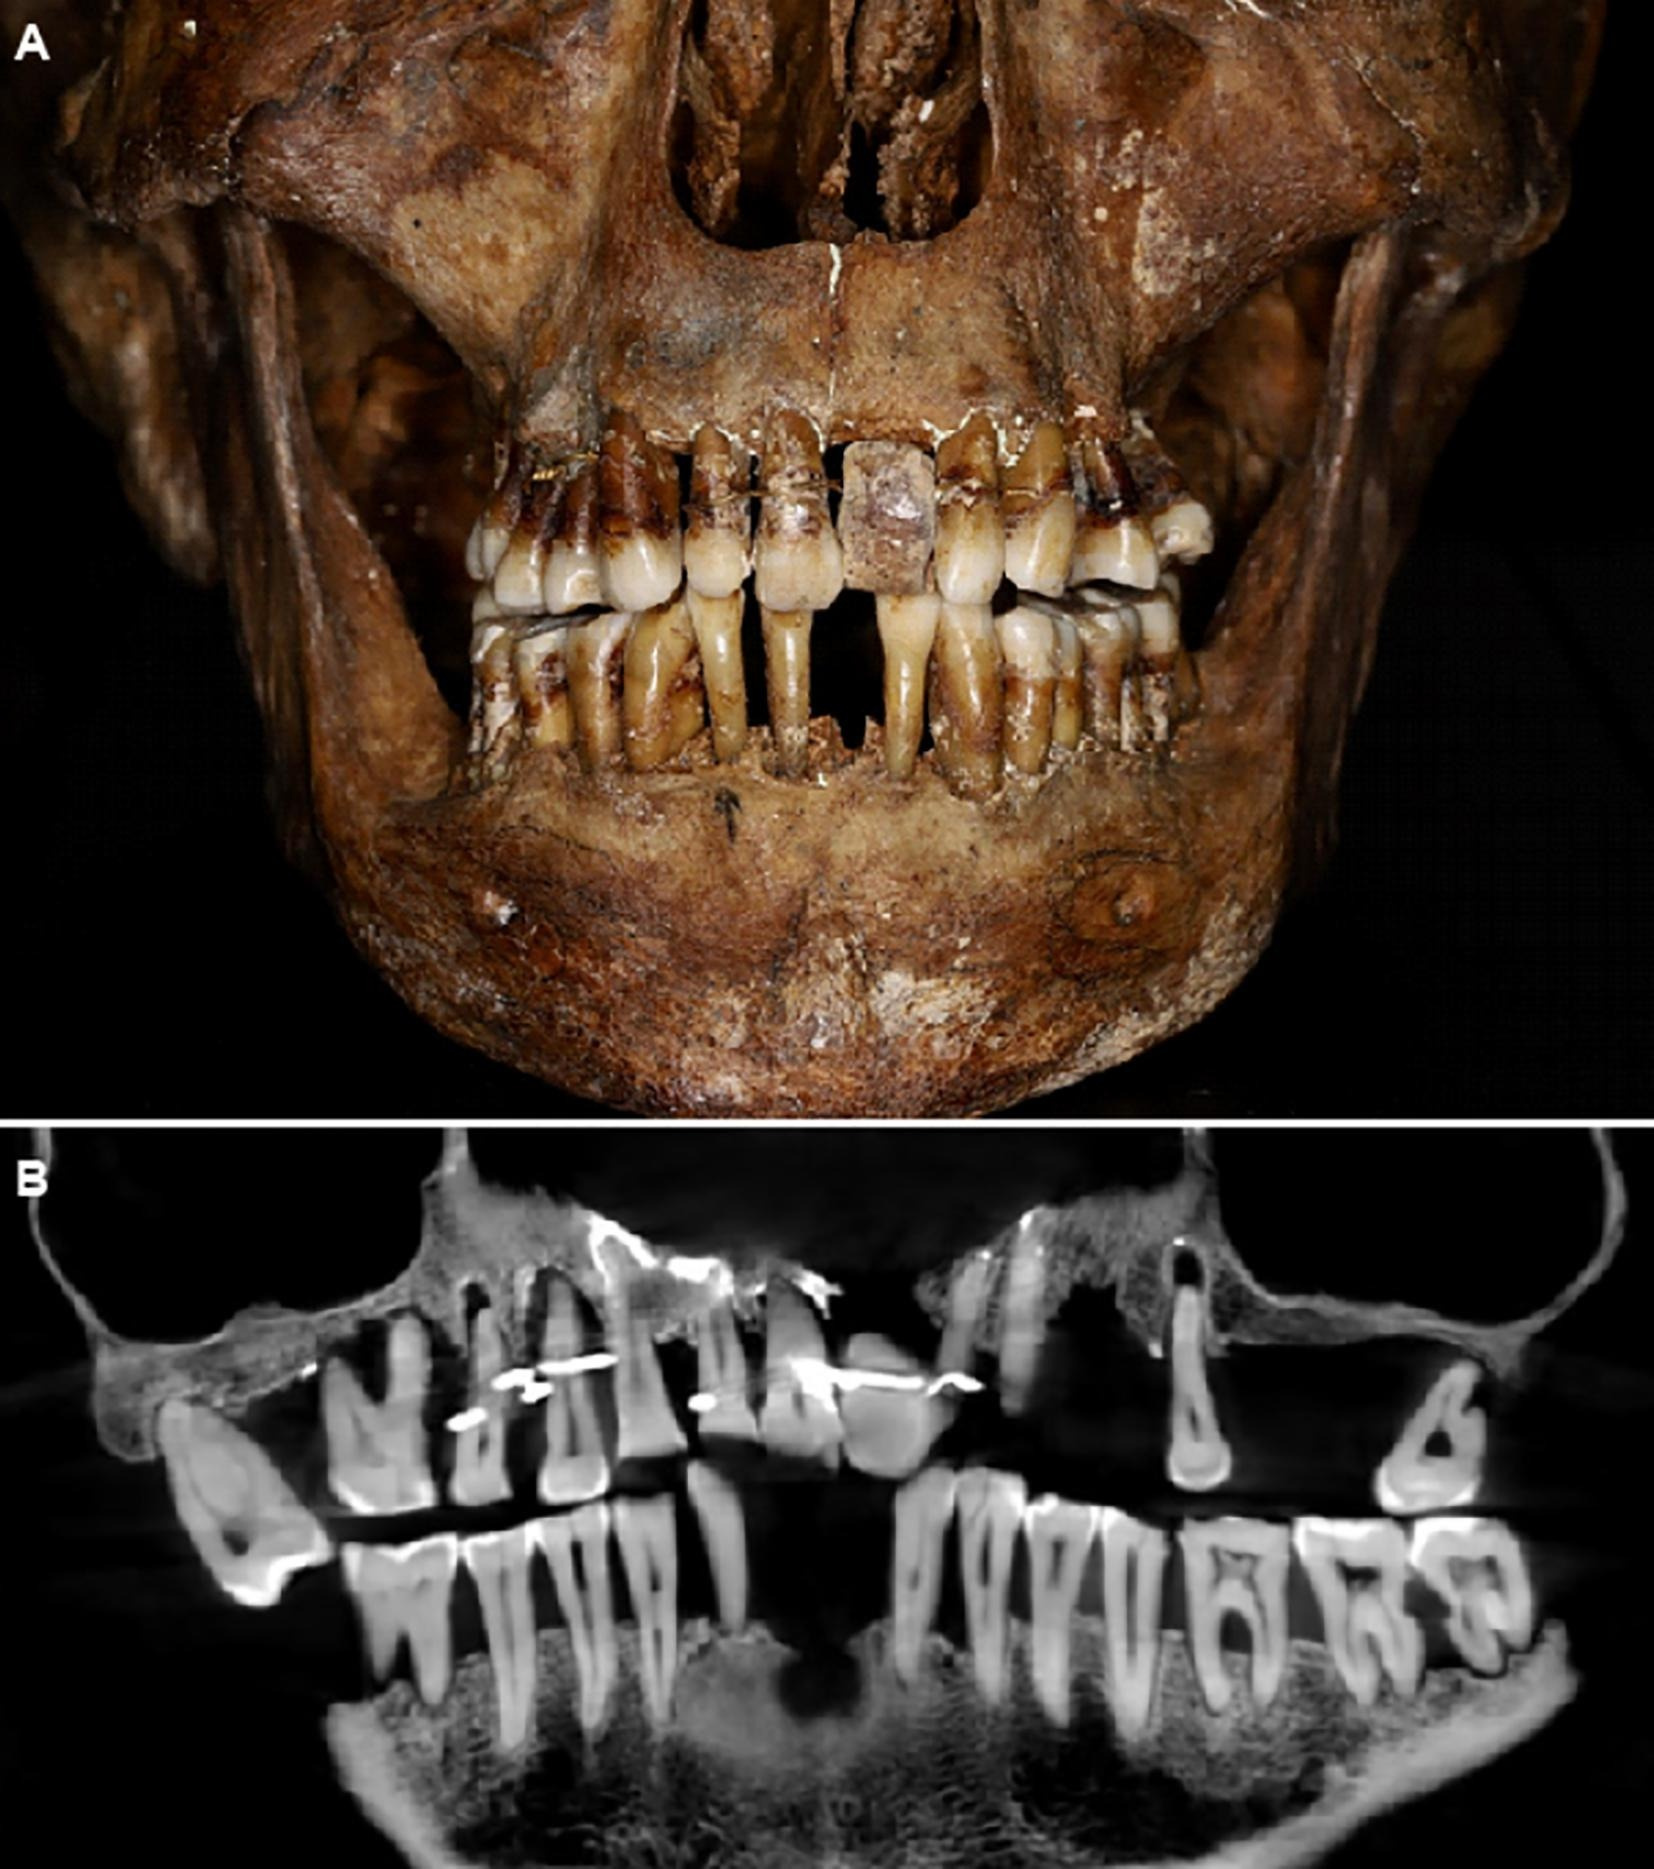

Спустя 400 лет после смерти французской аристократки XVII века ученые раскрыли ее тайну: она использовала золотую проволоку, чтобы предотвратить выпадение зубов.

Тело Анны д'Алегри, умершей в 1619 году, было обнаружено во время археологических раскопок в замке Лаваль на северо-западе Франции в 1988 году. Сообщалось, что ее скелет и зубы, забальзамированные в свинцовом гробу, оказались в хорошей сохранности для изучения. Еще при раскопках археологи заметили, что у женщины был зубной протез, однако исследователям не хватало передовых инструментов сканирования, чтобы узнать больше информации о проблемах ее здоровья.

35 лет спустя команда археологов и стоматологов установила, что Анна д'Алегри страдала пародонтитом, из-за которого ее зубы расшатывались, и выяснила, как аристократка справлялась с недугом.